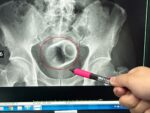

患者透過藥物、熱療與電療,加上體外震波治療(如圖)三週後,症狀明顯改善。 圈起來為棘上肌,上方周邊亮光處即爲鈣